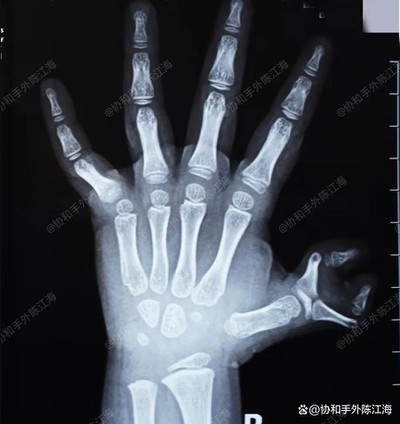

La mà dreta del nen té sis dits, amb els dos polzes severament corbats, formant el que sembla que les arpes de cranc es coneixen com a comunicació"Crab-claw Polidactyly."

Quan la petita utilitza la mà, els dos polzes convergeixen cap al centre, que no només afecta greument l’aspecte, sinó que també afecta significativament l’escriptura i la comprensió. Per tant, la cirurgia precoç és necessària.

Raig X preoperatòria